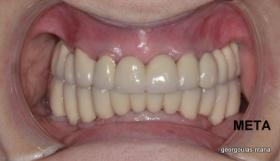

Η ασθενής αυτή είχε παλιές ακίνητες αποκαταστάσεις (γέφυρες) στην άνω γνάθο  κ μια κινητή προσθετική αποκατάσταση (μερική οδοντοστοιχία-"μασελάκι") στην κάτω γνάθο. Ήταν δυσαρεστημένη τόσο με την εμφάνιση όσο και με τη λειτουργία των δοντιών της καθώς παραπονιόταν ότι  είχαν εντονη κινητικότητα ενώ και οι προσθετικές τους εργασιές δεν ήταν σταθερές. Η πρόγνωση των δοντιών κρίθηκε φτωχή με αποτέλεσμα να μην είναι δυνατή η συμμετοχή τους σε μια νεα προσθετική αποκατάσταση με μακροχρόνια διάρκεια. Η ασθενής επιθυμούσε οι νέες αποκαταστάσεις να είναι σταθερές και ακίνητες.  Για το λόγο αυτό αποφασίστηκε η ολική αποκατάσταση της άνω κ κάτω γνάθου με ακίνητες επιεμφυτευματικές εργασίες. Στην αριστερή πλευρά της άνω γνάθου, λόγω μη επαρκούς οστού για την τοποθέτηση εμφυτευμάτων προηγήθηκε επέμβαση ανοιχτής  ανύψωσης ιγμορείου άντρου με τη χρήση πιεζοχειρουργικού μηχανήματος ώστε να δημιουργηθεί το κατάλληλο οστικό υπόστρωμα. Ακολούθησε σε επόμενο χειρουργείο η εξαγωγή των υπάρχοντων δοντιών κ η άμεση τοποθέτηση εμφυτεύματων (άμεση εμφύτευση) κ δύο μέρες μετά η τοποθέτηση προσωρινής εργασίας επί των εμφυτευμάτων (άμεση φόρτιση) με αποτέλεσμα η ασθενής να μη μείνει καθόλου χωρίς δόντια κ να είναι καλυμένη αισθητικά όσο καιρό διήρκησε η εργασία